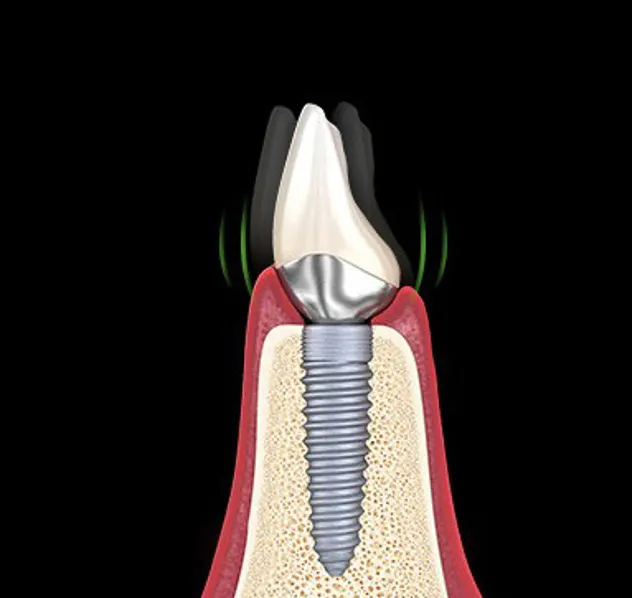

나사만 풀린경우

나사를 다시 조입입니다.

필요 시 임플라트 머리를

다시 제작합니다.